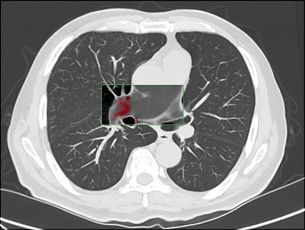

Einstein Healthcare Network United States Dr. Terence Matalon, Dr. Thomas Reilly, & Team “On a non-contrast CT chest, IMR allowed for improved visualization of hyper-dense thrombus in the pulmonary artery (pulmonary embolism). This was confirmed with subsequent contrast enhanced CT.”

Parameters: kVp: 120 mAs: 50 Scan length: 27.5 cm Scan time: 2.2 sec CTDIvol: 3.3 mGy DLP: 90.7 (mGy*cm) Scanner: iCT Dose: 1.7 mSv* *AAPM Technical Report 96